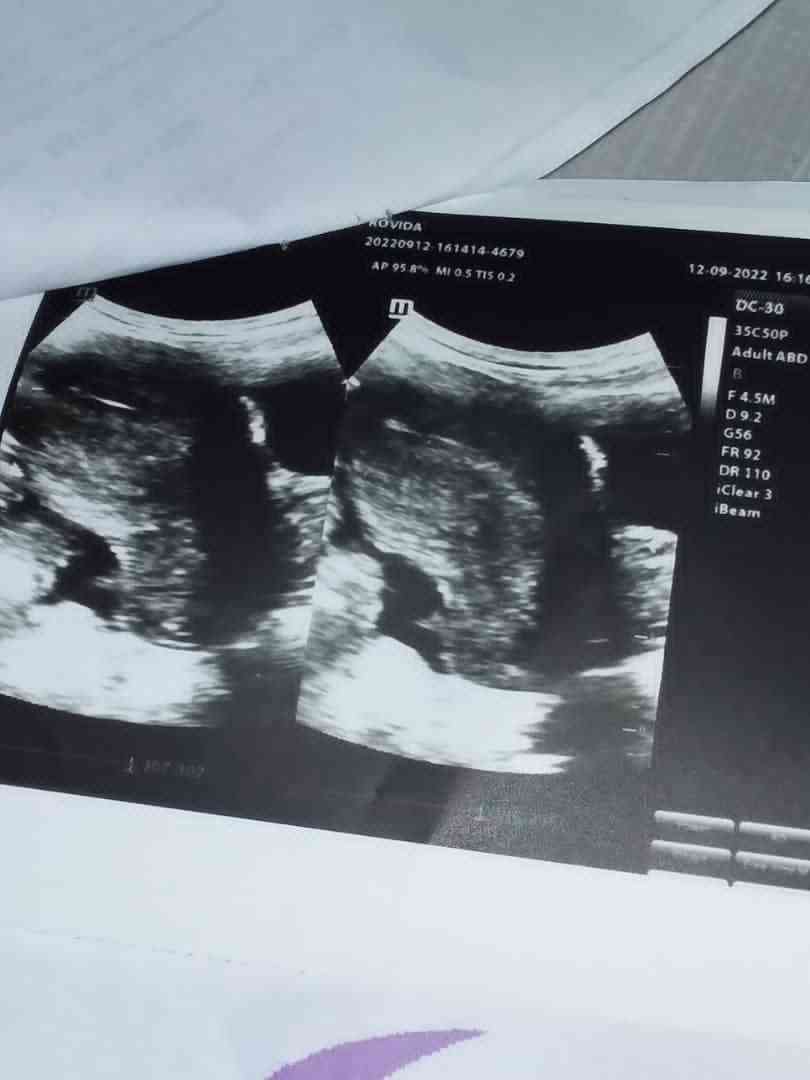

هل هم توام او جنين دكتورة ماقالت لي اريد أن اتاكد